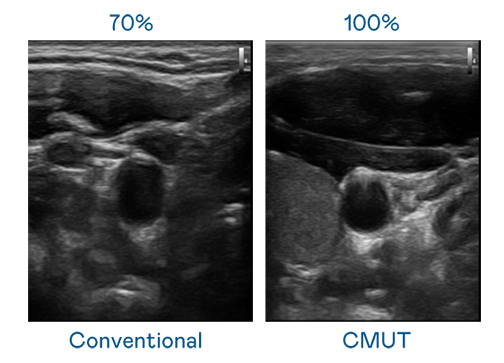

CMUT 技术是一种用电容式微机电元件来产生超音波讯号的技术。与传统 PZT 压电式技术相比,CMUT 频宽增加 30%,更宽频的超音波讯号让影像解析度大幅提升,是实现高影像品质医疗超音波扫描、促进精准医疗发展的关键技术。

大频宽带来超清晰影像

超音波影像的解析度高低,首先取决于探头能发出的讯号频宽。Vsport CMUT 可提供高清晰的超音波讯号,提供高频宽、高灵敏度、影像纹理细节更高的超音波影像,协助医护人员缩短影像判读时间及利用精准的医疗影像进行诊断。